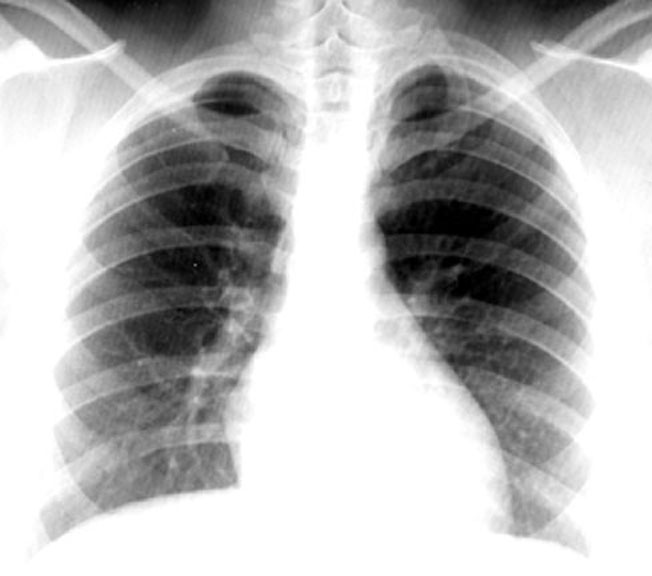

weekly clinical round for undergraduate from 8 to 11 AM during which interpretation of CHEST X rays was done for all cases of cardiothoracic surgery, gived by 2 staf member for 3 months